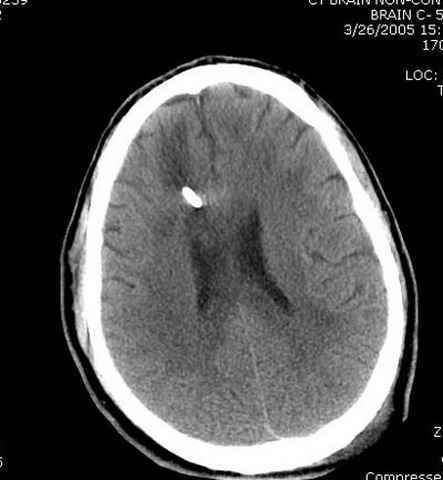

Наблюдается службой травмы и нейрохирургии (ICP) Increased Intracranial Pressure by ventricular cateter

больной без сознания, со слов нейрохирурга, наблюдается положительная динамика в нейрохирургическом статусе.

-Согласен, рана до прихода пластического хирурга была 38х13 см, можно было постараться закрыть сверху, а в нижнем отделе где был ожог, применить кожную пластику меньшим размером. К моему удивлению и разочарованию, когда вернулся из другой операционной (шли пареллельные операции), он уже успешно заканчивал свое дело. Кстати недавно разговаривал с нейрохирургом, он снял ICP (intracranial prеssure monitor), внутричерепное давление стабилизировалось, ортопеды и хирурги закончили с лечением, теперь длительное неврологическое восстановление.

Было множество случаев, когда безнадежные больные с повреждением головного мозга через пару месяц приходили в сознание, поэтому уделяем внимание на ургентность стабилизации переломов костей скелета.